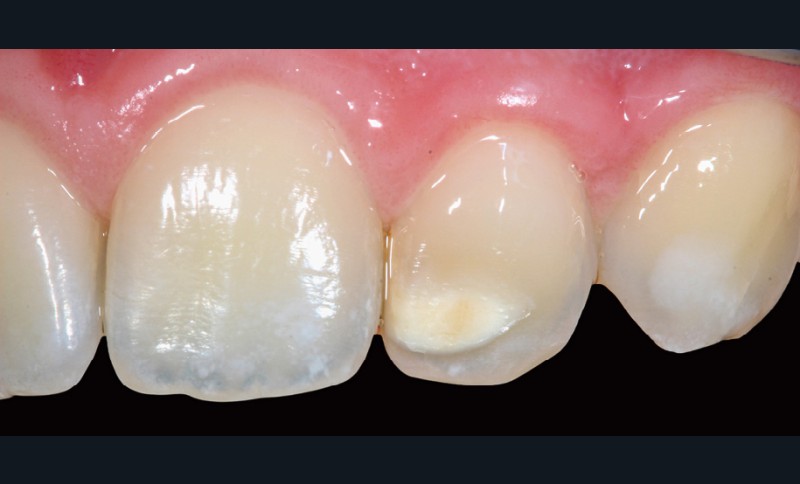

– Fluorose légère, hypominéralisation de l’émail (fig. 8).